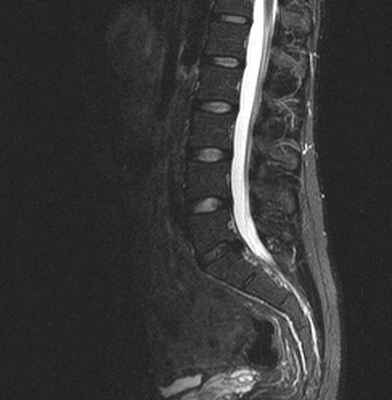

КТ. Перелом тела С2 (красные стрелки).

Особую категорию составляют пациенты, у которых, несмотря на наличие неврологической симптоматики, не выявляется изменений при рентгенографии или КТ. Число таких пациентов составляет около 10%. Среди различных механизмов подобных травм наиболее вероятна кратковременная компрессия спинного мозга задней продольной связкой и дисками, либо, жёлтой связкой и пластиной дуги. Посколько резкие сгибания и разгибания наблюдаются при высокой подвижности в сегментах, такие травмы более вероятны в шейном отделе позвоночника. Спондилолиз усугубляет эту ситуацию, приводя к центральному синдрому спинного мозга. В этих случаях необходимой является МРТ позвоночника. Характерными находками, которые мы часто видим при травмах при МРТ в СПб, являются отёк спинного мозга и гематома, причём последняя при МРТ позвоночника плохим прогностическим фактором в отношении восстановления неврологического дефицита. К наиболее тяжелым осложнениям шейной травмы относится расслоение магистральных артерий, определяемое по МРТ, МРА или КТ и КТА. В высоком поле такой вид травм лучше виден чем в открытом МРТ. МРТ СПб позволяет выбирать место МРТ, однако, острая травма шейного отдела позвоночника требует высокоспециализированного нейрохирургического отделения

МРТ шейного отдела позвоночника. Острая травма. Компрессия спинного мозга, отек и контузия. Сагиттальная Т2-взвешенная МРТ.